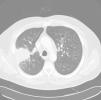

A 52-year-old man, active smoker, presented with a 15-day history of fever, general malaise and bloody expectoration. Isolated crepitating rales were heard on lung auscultation. Chest X-ray showed right upper lobe condensation and enlarged right hilum. Treatment with levofloxacin was prescribed, but improvement was limited, so a chest computed tomography (CT) was performed, revealing condensation with air bronchogram in the posterior segment of the right upper lobe (Fig. 1), and enlarged right hilar, retrocava-pretracheal and prevascular lymph nodes. Bronchoscopy was performed: gross results were normal, and cytology and bacilloscopic results from bronchial aspirate were also normal. CT-guided core biopsy of the lung was conducted, and histologic analysis of the specimen showed granulomas with multinucleated giant cells and epithelioid cell histiocytes, some of which had central necrosis. Treatment began with isoniazid, rifampicin, pyrazinamide and ethambutol. Mycobacteria were subsequently isolated from the culture of the bronchial aspirate; these were identified as M. interjectum using DNA technology based on inverse hybridization of PCR products targeting the 23S rRNA gene (GenoType®Mycobacterium CM). The patient's progress was satisfactory and, 2 months later, cultures were negative for mycobacteria. Pyrazinamide and ethambutol were withdrawn, while isoniazid and rifampicin administration continued for 1 year. At that time, the patient remained asymptomatic, with fibrous scarring and infiltration in the right upper lobe on chest X-ray. Currently, 20 months later, he is stable with no signs of disease reactivation.